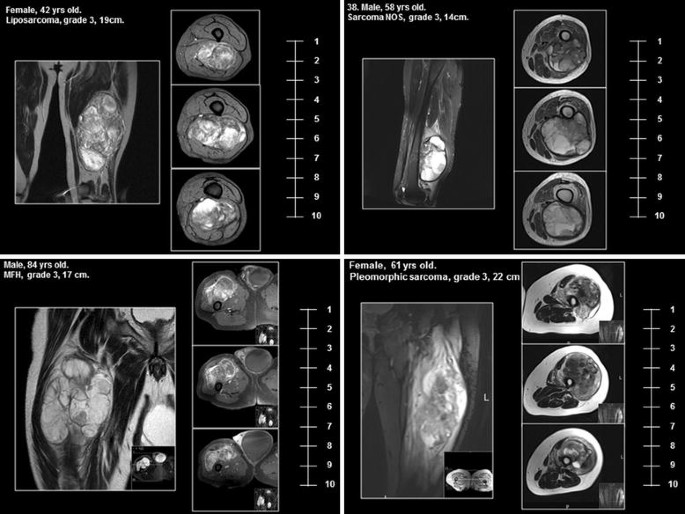

To ensure that the tumours in both cohorts were equivalent in terms of resectability, three independent sarcoma surgeons working at major European sarcoma centres reviewed anonymised MRI’s from patients within each cohort and scored the compatibility of the tumours with limb-conserving surgery and adjuvant radiotherapy alone. Twenty patients were randomly selected from each cohort. The anonymised images, together with basic patient details (gender, age, histopathology and tumour size), were then distributed to the assessors who ranked the images based on resectability from 1 to 10, with 1 being easily resectable by limb-conserving surgery and 10 indicating that limb conservation was impossible and amputation was required (Fig. 1).

Details of patient demographics are shown in Table 1. 80 patients were identified in the Standard cohort and compared to 44 patients in the ILP cohort (Fig. 2). The median age of patients in the Standard cohort was 60.5 years (range 18–92), which was significantly older than the ILP cohort with a median age of 56 years (range 17–82), (Mann–Whitney test p = 0.033). There was no difference in tumour size between the two cohorts with both having a median tumour size of 13 cm (Standard range 10–29, ILP range 10–34), (p = 0.915 Mann–Whitney test). The proportion of grade 2 and 3 tumours was also similar with the Standard cohort having 52 (65%) of patients with grade 3 tumours and the ILP cohort 31 patients (70.5%) (p = 0.840 Fisher’s exact test). No significant difference was found in the score of resectability between the two groups (Standard Cohort vs ILP median 4.45 vs 5.05 p = 0.314, mean 5.12 vs 4.23 p = 0.112) although the ILP cohort had slightly higher absolute scores (Additional file 1: Figure S1).